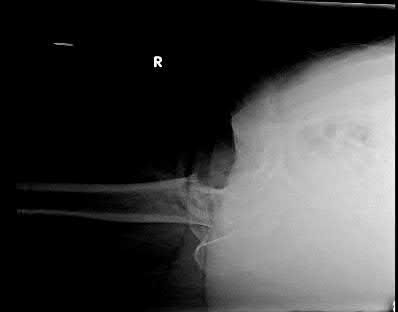

A 25-year-old female is involved in a motor vehicle collision. She presents with the isolated injury seen in Figures A through D. Her leg is swollen but her skin is intact. She has no clinical signs of compartment syndrome. Which of the following treatment options will allow for maintenance of fracture alignment and minimize the risk of soft tissue complications?

The patient presents with a closed distal third metaphyseal-diaphyseal distal tibia fracture with simple intra-articular extension. Immediate intramedullary nailing along with percutaneous fixation of the articular component provides appropriate restoration of length, rotation and alignment and minimizes the risk of wound complication.

Displaced distal third tibia fractures may be associated with simple intraarticular extension. Operative treatment of intra-articular distal tibia fractures has historically been performed with open reduction and internal fixation. Early open reduction and plate fixation of pilon fractures has been associated with high rates of infection and wound complication. In select patterns with simple articular extension, percutaneous screw fixation and medullary nailing may provide appropriate reduction with minimal soft-tissue risk.

Marcus et al. evaluated the outcomes of immediate intramedullary nailing and percutaneous fixation of simple intra-articular distal tibia fractures (AO/OTA 43 C1 and C2). The authors found excellent rates of union and alignment, however caution against broad application of this technique until more rigorous randomized studies can be performed.

Sirkin et al. retrospectively evaluated the results of a staged approach to management of intra-articular distal tibia fractures with temporary bridging external fixation followed by open reduction and internal fixation (ORIF). The authors found decreased rates of wound complication and infection compared with prior studies.

Figures A and B demonstrate a distal third tibial shaft fracture with simple intra-articular extension. The axial and coronal CT cuts in Figures C and D further clarify the articular injury. Illustrations A and B demonstrate a comminuted distal third tibial fracture with simple intra-articular extension. Illustrations C and D are fluoroscopic images of the same injury after intramedullary nailing and percutaneous fixation of the articular component.